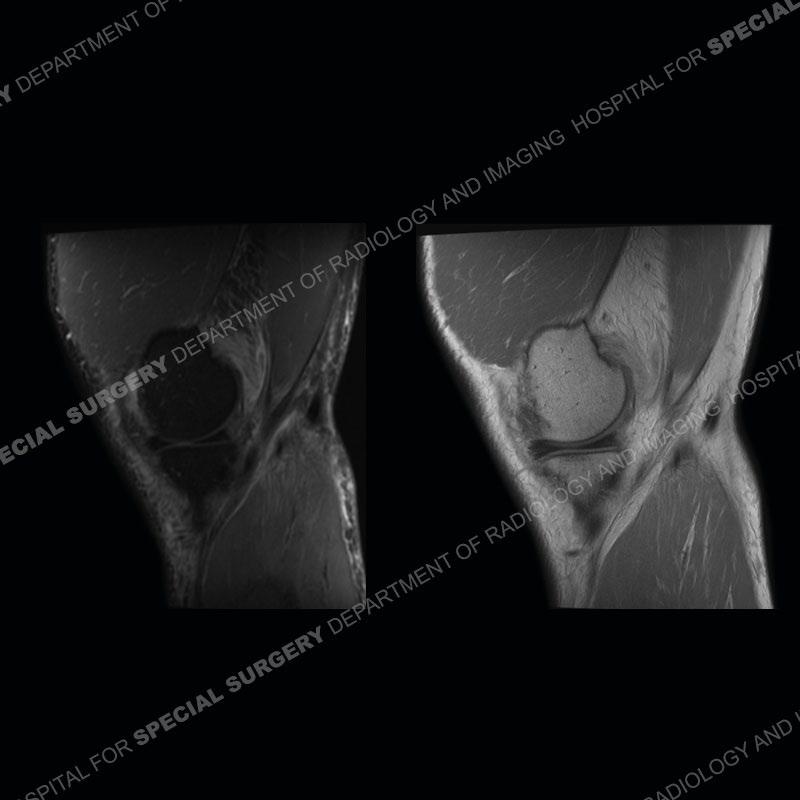

The radiographs show degenerative change of the medial compartment and a varus knee, but they are not germane to this case. No acute bony injury is present. The MRI shows edema of the posterior medial knee/soft tissue and a focal area of a partially disrupted low signal structure. The details are kept at a minimum in the findings of this case on purpose.

Fourth, use all imaging planes and different pulse sequences to make your diagnosis. The edema highlighted in this case can be seen as the obscuration of fat on the PD images but is much easier to perceive as the high signal on the IR pulse sequences. The actual disruption of the MHG myotendinous junction is only able to be seen on the axial images. On the sagittal and coronal images, we get a sense something is wrong but hard to be exact. Lastly, when you look at a study and something just seems off (as I would say the sagittal and coronal images do with that dark band of tissue posteriorly), listen to yourself and go through the study slowly and meticulously. Most of the time you will find you were right, and something indeed is present.